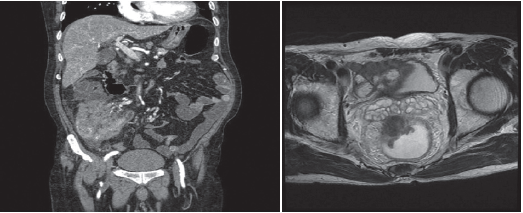

2. 전산화 단층촬영(CT)

주로 대장암을 진단하고 암이 주변 장기나 간, 림프절 등으로 전이 되었는지 알아보는데 가장 널리 사용되는 검사입니다. 검사 전날 특별한 처치는 필요하지 않으며 검사 당일 8시간 정도의 금식이 필요하고 정확한 검사를 위해 정맥 주사를 통해서 조영제를 주입 받고 검사를 받습니다. 이때 신장의 기능이 떨어져 있는 환자나 조영제에 알레르기 반응, 즉 조영제 주사 후 심한 구토, 피부 발적, 두드러기, 가려움증, 목이 붓고 쉬는 듯 한 증상을 보인 적이 있는 환자는 검사 전에 담당의사와 상의해야 합니다.

3. 자기공명영상(MRI)

MRI 검사는 CT검사에서 간 전이가 명확하지 않거나 간으로 전이된 암의 개수를 정확히 파악하고자 할 때 보조적으로 사용됩니다. 직장암 환자에서 시행하는 MRI의 경우, 직장 주변으로 암이 얼마나 퍼졌는지 알아보는데 유용하여 직장암 진단 후 치료 방침을 결정하는데 도움이 됩니다. CT검사와 다른 종류의 조영제 주사를 이용하므로 CT검사에서 사용되는 조영제에 부작용 반응을 보이는 경우에도 검사할 수 있습니다. 그러나 검사비가 비싸고, 검사 시간도 CT검사에 비해 길며, 좁은 원통형 공간에 들어가 검사를 하므로 폐쇄 공포증이 있는 경우에는 검사를 하기 어렵습니다.